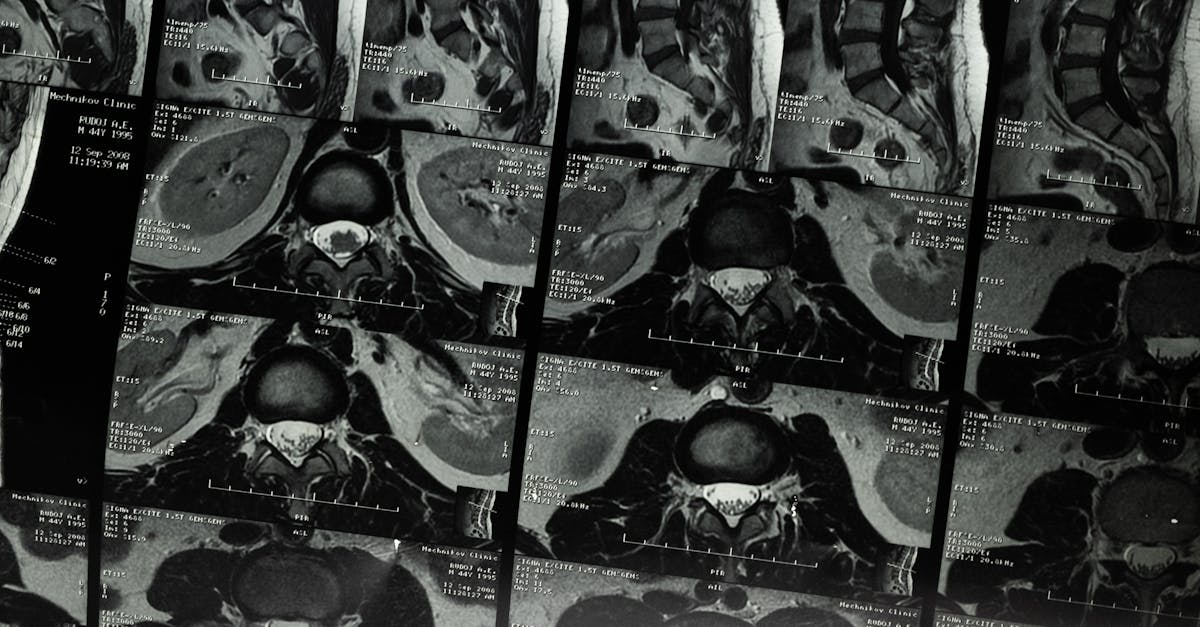

MRI, short for Magnetic Resonance Imaging, and X-Ray are two common medical imaging procedures used for diagnosing various health conditions. When deciding between the two, one factor to consider is the type of information needed. MRI provides detailed images of soft tissues, organs, and internal structures, making it suitable for detecting abnormalities such as tumors, injuries, and abnormalities in the brain and spinal cord. On the other hand, X-Ray is ideal for capturing images of bones, teeth, and certain organs like the lungs, making it useful for identifying fractures, infections, and conditions like pneumonia.

MRI differs from other types of medical imaging, such as X-rays and CT scans, in that it does not use ionizing radiation to produce images. Instead, MRI relies on magnetic fields and radio waves to create detailed cross-sectional images of the body's organs and tissues.

Healthcare providers may recommend an MRI over other imaging techniques when more detailed images of soft tissues, such as the brain, muscles, and joints, are needed. MRI is particularly useful for diagnosing conditions like brain tumors, spinal cord injuries, and joint disorders.